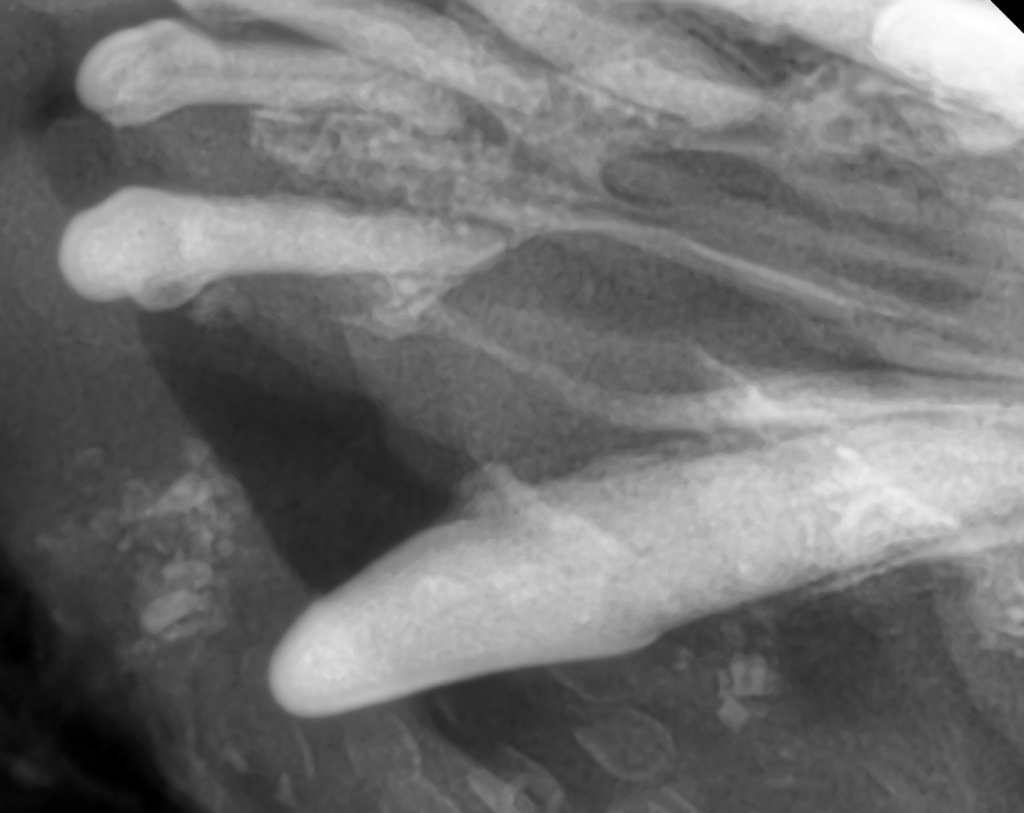

麻酔下での口腔内精査と歯科レントゲンにて、上顎骨の骨融解を認め、鼻腔との交通(口腔鼻腔瘻)**が確認されました。

なお、歯肉退縮は明らかでなかったため、歯周病の進行が外見からはわかりにくい「隠れ歯周病」のパターンといえます。